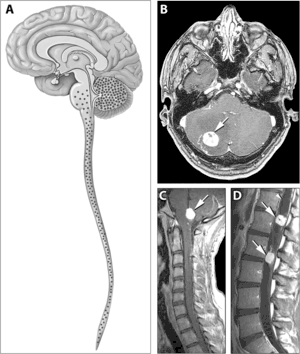

| Typical distribution of hemangioblastomas in Von Hippel–Lindau disease | |

Signs and symptoms associated with VHL disease include headaches, problems with balance and walking, dizziness, weakness of the limbs, vision problems, and high blood pressure. Conditions associated with VHL disease include angiomatosis, hemangioblastomas, pheochromocytoma, renal cell carcinoma, pancreatic cysts (pancreatic serous cystadenoma), endolymphatic sac tumor, and bilateral papillary cystadenomas of the epididymis (men) or broad ligament of the uterus (women).[6][7] Angiomatosis occurs in 37.2% of patients presenting with VHL disease and usually occurs in the retina. As a result, loss of vision is very common. However, other organs can be affected: strokes, heart attacks, and cardiovascular disease are common additional symptoms.[5] Approximately 40% of VHL disease presents with CNS hemangioblastomas and they are present in around 60-80%. Spinal hemangioblastomas are found in 13-59% of VHL disease and are specific because 80% are found in VHL disease.[8][9] Although all of these tumours are common in VHL disease, around half of cases present with only one tumour type.[9]